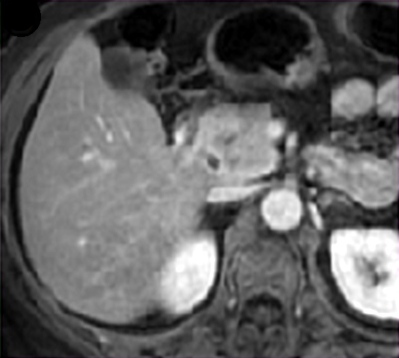

Magnetic Resonance Imaging (MRI) of the Abdomen

MRI (Figure 3) is recommended to request a MRI to all the patients with suspicion of SPN of the pancreas, besides the CT of the abdomen, in order to avoid possible diagnostic mistakes [1, 12, 16, 17, 24]. MRI presents information about images related to contrast behavior (understrapper), after it is administered. This information is similar to that of the CT. However, MRI add information that enable better determining the lesion’s resectability, the presence and integrity of the capsule (discontinuities), internal blood products and the cystic component [1, 12, 16, 17, 24]. The inherent features of the MRI method are characterized by the depiction of circumscribed and hypo-intense lesions in T1. However, still in T1, after the intravenous administration of gadolinium during the arterial phase, the lesion becomes progressively and slight enhancement, with heterogeneous aspect. But in the venous and late phase, the lesion gets little intense (Hypo-intense) due to the fact that the contrast gets little perceptible [12, 16, 17]. The solid tumors get gradually more strength. The cystic tumors were insignificantly enhanced during the portal venous and delayed phases [12]. However, these lesions appear hyper-intense in T2 [12, 16, 17].

|

Figure 3. Magnetic resonance imaging of the abdomen in Case #9 showing the tumor. |

Sixty percent (60%) of our patients were diagnosed with SPN of with the use CT and MRI scans of the abdomen (Table 2 and Figures 2a and 3). All the patients in our cohort had normal values of the following laboratory studies: complete blood count, coagulation panel (Prothrombin time; International normalized ratio; Partial thromboplastin time; Number of platelets; Bleeding time) amylase, serum creatinine, blood urea, serum albumin, liver profile and also had normal pre-operative tumor markers (like CEA and CA 19.9). The anatomic and pathological examination corroborated the diagnosis of SPN in 90% of the cases. Immunohistochemical studies were necessary to get the final diagnostic confirmation in only one case.